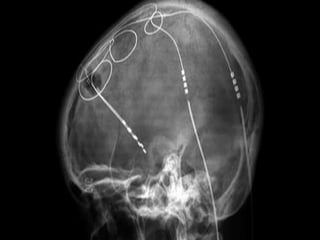

SURGICAL

MANAGEMENT:

•1. DEEP BRAIN

STUMULATION